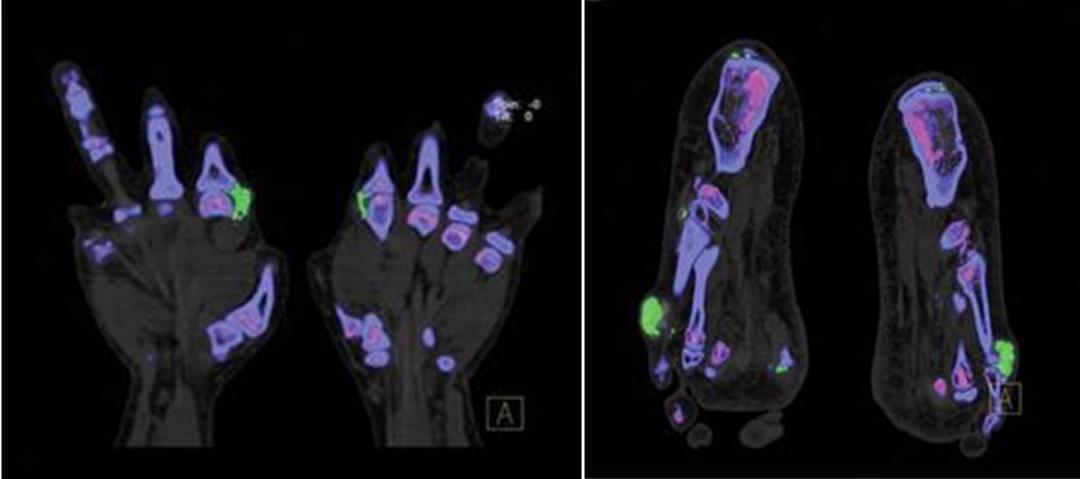

双腕、手及双足部分关节周围可见软组织不对称结节肿胀,密度稍增高;部分关节面下及边缘见部分囊状、穿凿样骨质破坏。

影像学检查对诊断痛风,评价病情有很大帮助,该患者双源CT,超声及X线均显示典型痛风改变,临床医生应合理应用这些敏感特意的影像学手段诊断、管理痛风。